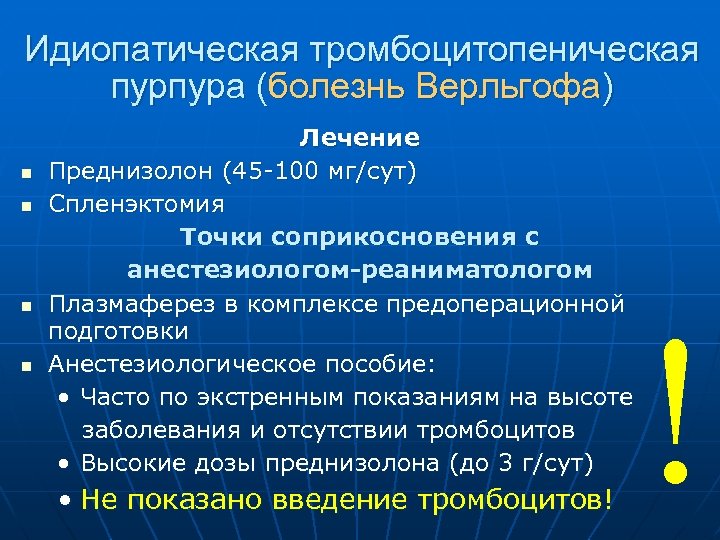

Идиопатическая тромбоцитопеническая пурпура (болезнь Верльгофа) n n Лечение Преднизолон (45 -100 мг/сут) Спленэктомия Точки соприкосновения с анестезиологом-реаниматологом Плазмаферез в комплексе предоперационной подготовки Анестезиологическое пособие: • Часто по экстренным показаниям на высоте заболевания и отсутствии тромбоцитов • Высокие дозы преднизолона (до 3 г/сут) • Не показано введение тромбоцитов! !